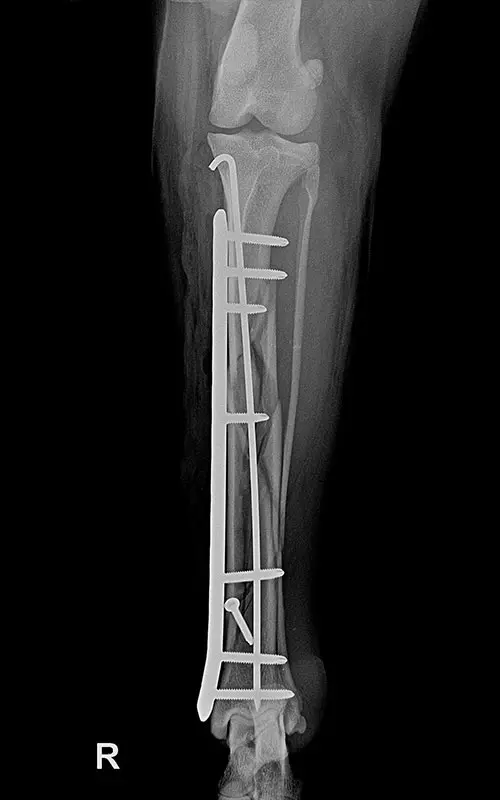

It is a common case where long tubular bones suffer multiple fractures and there is no bone lying on top of each other after repositioning that would aid in stability after fixation. The K-wire-and-plate combination already known during DCP plating can also be used for locking plating:

- Among locking systems, only the polyaxial system is fully suitable for this task, because during the insertion of srews the medullary nail can be bypassed (cf. in monoaxial systems, if the nail is under the plate hole, no screw can be inserted in that hole).

In our case, a 10-year-old labrador is involved in a car accident and his left femur and right tibia are severely injured. The dog had difficulty moving anyway due to severe hip arthrosis. During one surgical narcosis, K-pin - polyaxial locking plating was applied to both bones, the larger fragments were also fixed with 1-1 lag screws.